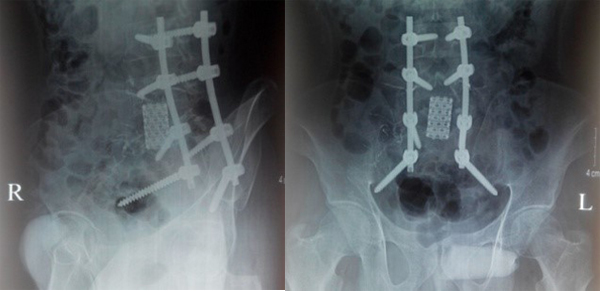

Bệnh nhân được phẫu thuật ngày 29/9/2015 với 2 đường mổ phía sau và phía trước. Với đường mổ phía sau, bệnh nhân nằm sấp, cố định nẹp vít các đốt L3L4S1-xương cánh chậu, sau khi bắt vít chúng tôi tiến hành cắt bỏ cung sau ngang cuống L5 để giải ép thần kinh, lấy bỏ phần u phá hủy cuống L5 hai bên, đặt rod, ốc khóa trong cố định và đặt 1 dẫn lưu. Kết quả sinh thiết tức thì: u TBKL độ 2. Thời gian phẫu thuật đường sau: 2 giờ 30 phút.

Mổ đường sau cố định cột sống, giải ép

Do khối u nằm ngay sau ngã ba chủ chậu nên chúng tôi đã phải bộc lộ tỉ mỉ để bóc tách u khỏi động mạch, tĩnh mạch và niệu quản. Khối u to nên chúng tôi phải lấy bớt một phần u để tiếp tục bóc tách tránh phải cắt mạch để bộc lộ. Sau khi lấy bỏ phần u xâm lấn ra trước, tiến hành cắt thân L5, đặt lồng titan có xương mác đồng loại và bột xương để ghép thay thế. Đặt một dẫn lưu sau phúc mạc và một dẫn lưu Douglas trước khi đóng bụng. Thời gian đường mổ phía trước 3 giờ 30 phút, tổng thời gian mổ 6 giờ.

Sau mổ bệnh nhân nằm điều trị hồi sức tích cực 2 ngày, về khoa điều trị ngày thứ 3. Rút dẫn lưu vết mổ lưng ngày thứ 3, rút sonde dạ dày và dẫn lưu bụng ngày thứ tư. Sau mổ một tuần có thể mặc áo nẹp ngồi dậy, đau ít. Cắt chỉ ra viện sau 2 tuần: hết đau lưng, có thể tự đi lại mà không cần người trợ giúp. Khám lại sau 3 tháng bệnh nhân đi lại tốt, hết đau.

Ngoài mục tiêu cắt bỏ rộng rãi khối u, việc bảo tồn chức năng thần kinh và tái tạo lại giải phẫu để đạt được sự ổn định trục và chức năng cơ học của cột sống là điều hết sức quan trọng [14]. Sau khi lấy toàn bộ thân L5, chúng tôi đặt lồng titan có xương mác đồng loại bên trong làm cầu xương thay thế, đảm bảo trục cũng như độ ưỡn cột sống.